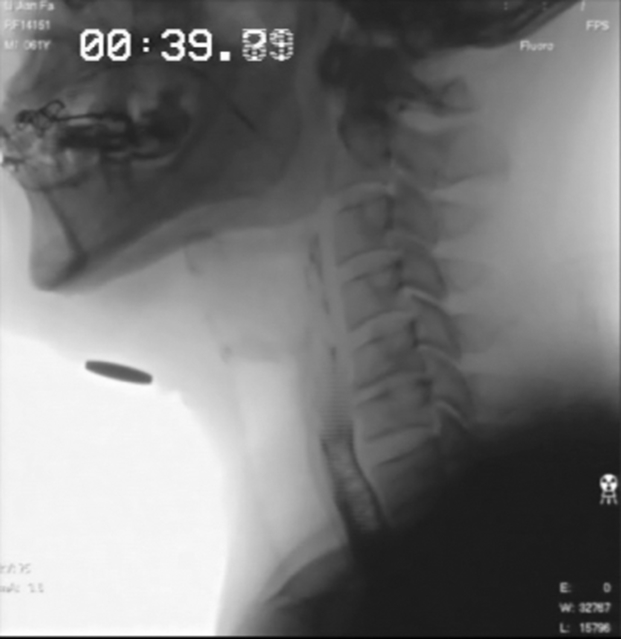

Fig. 1.

Two pictures of the highest position of the hyoid and the lowest position of the hyoid were copied into one picture. The maximum displacement of the hyoid bone (white arrow) can be measured. The black arrow indicates the jiao coin (i.e., renminbi [RMB], the 2010 version) with a diameter of 1.9 cm.